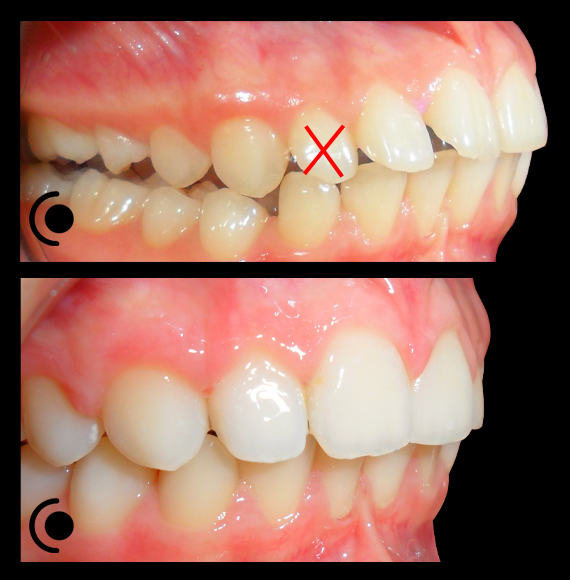

O našoj kvaliteti najbolje govore naši rezultati!

Centar za ortodonciju Petra Džapo